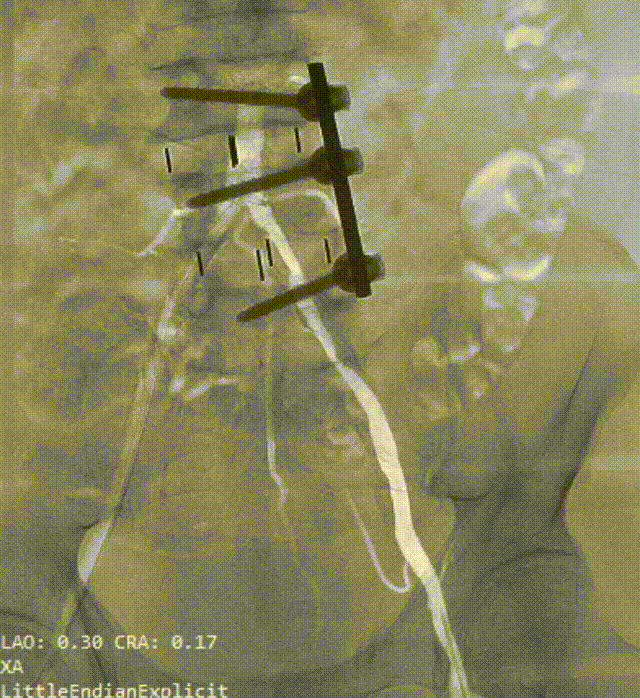

入路造影显示左髂总动脉-左股总动脉严重狭窄伴钙化

确认狭窄位置

送入v18导丝建立通路

送入6.5×60mm赛禾外周冲击波球囊

定位最狭窄处充盈至4atm进行脉冲治疗

脉冲释放一个周期(20秒)后,将冲击波球囊加压至6atm并保持球囊扩张30秒,造影显示腰征消失,血管顺应性被改善

复查造影显示左髂总动脉-股总动脉狭窄较前明显减轻,管腔直径预估达到输送大鞘的要求